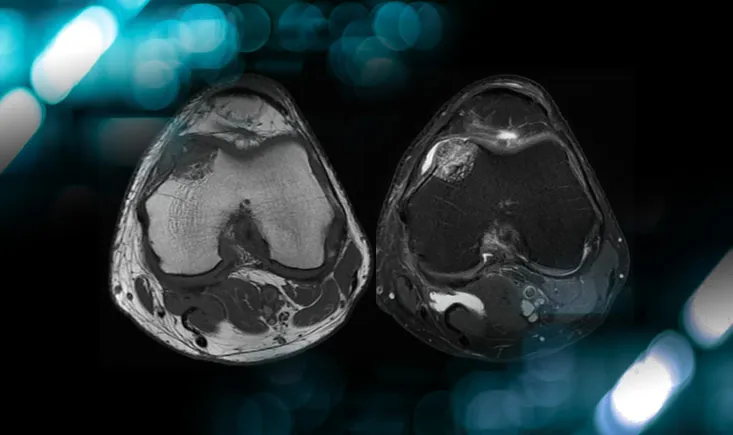

Management of an osteolytic lesion of the distal femur affecting the knee joint

Explore the case of a patient with knee pain, revealing more than just an injury, and uncover the management strategies for osteolytic lesions…

Explore the case of a patient with knee pain, revealing more…